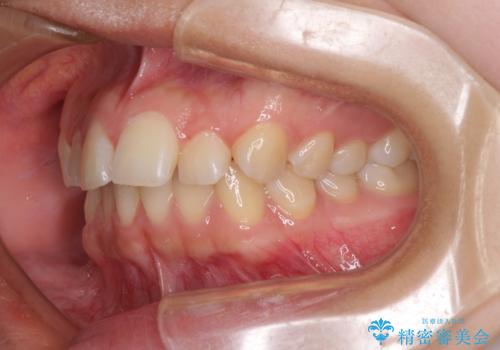

- 前歯の叢生を気にして来院された患者様です。

奥歯の咬み合わせを見ると、上顎が下顎に対して相対的に前方にあり、上下の前歯が接触していない状態でした。

咬み合わせを改善するためには、上顎臼歯を後方に移動させた咬み合わせにする必要があります。

インビザライン単体で改善することも可能ですが、咬合力が強く、単位で達成する可能性が低いと考えられたため、カリエール・ディスタライザーという補助装置を併用して、より確実性を上げることとしました。

奥歯の咬み合わせを改善しながら、並行してインビザラインで歯列を整えることとしました。

カリエールディスタライザーを併用したことで、確実かつ短期間で治療を終えることができました。